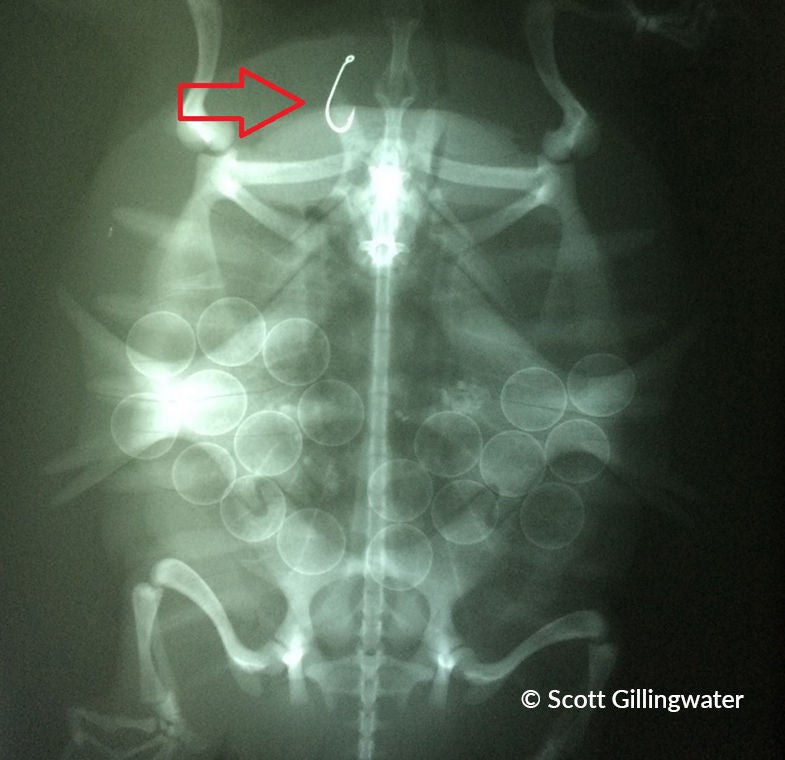

Tortue serpentine avec hameçon dans la bouche

Tortue-molle à épines avec hameçon dans la bouche

Certains hameçons restent pris dans la bouche de la tortue, ce qui nuit à sa capacité de s’alimenter. D’autres hameçons sont avalés et demeurent logés dans la gorge ou l’estomac, ce qui peut être mortel. Même si ce n’est pas l’hameçon qui tue la tortue, elle peut mourir d’intoxication au plomb si elle avale aussi le plomb.

Les études démontrent que l’hameçonnage accidentel de tortues est courant et répandu. Les tortues serpentines sont l’espèce la plus souvent hameçonnée, sûrement en raison de leur taille, leur aire de répartition élargie et leurs habitudes d’alimentation. D’autres espèces qui se font souvent hameçonner sont la tortue géographique, la tortue peinte, la tortue-molle à épines et la tortue des bois.